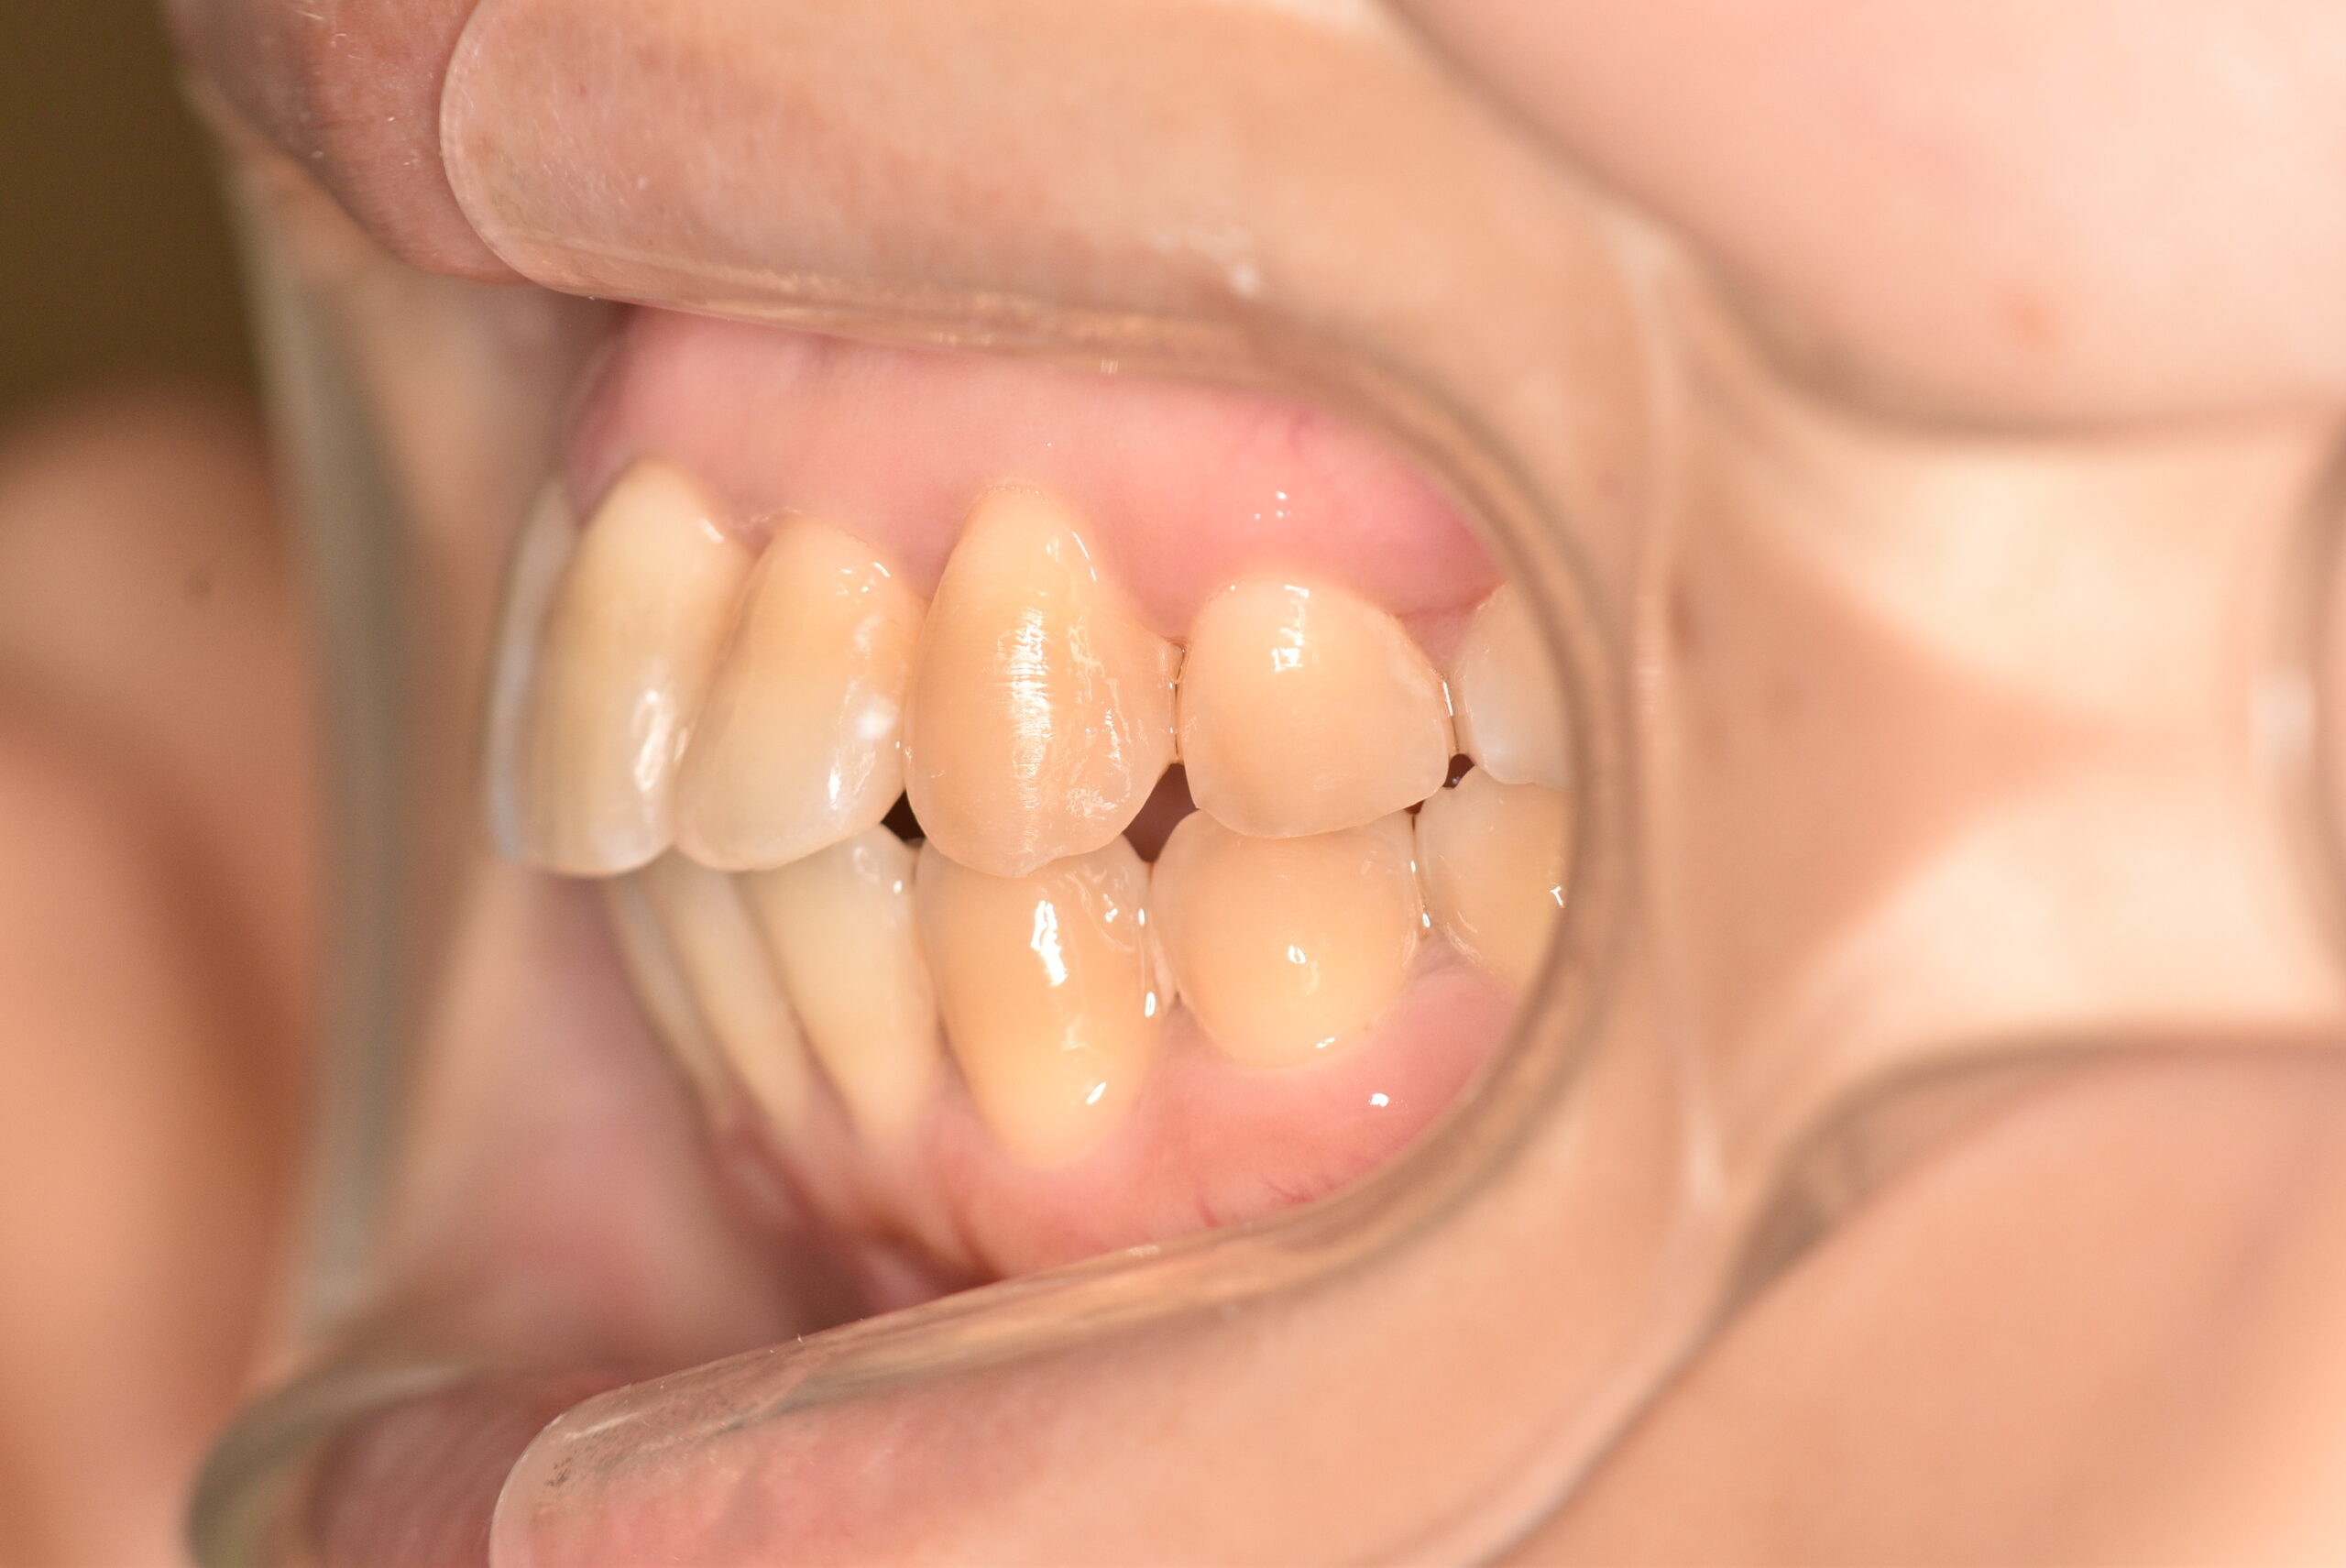

| 治療内容の詳細 | 初診時31歳の女性で、前歯が奥側にあることを気にされ来院されました。 検査の結果、上下顎叢生を伴うアングルⅠ級不正咬合と診断しました。 治療としては、上顎臼歯部の遠心移動を行い、歯を配列するためのスペースを確保し、非抜歯の上、セルフライゲーションブラケット装置(デーモンシステム)で歯の配列と咬合関係の改善をを行いました。 治療期間は、2年7ヶ月でした。 |